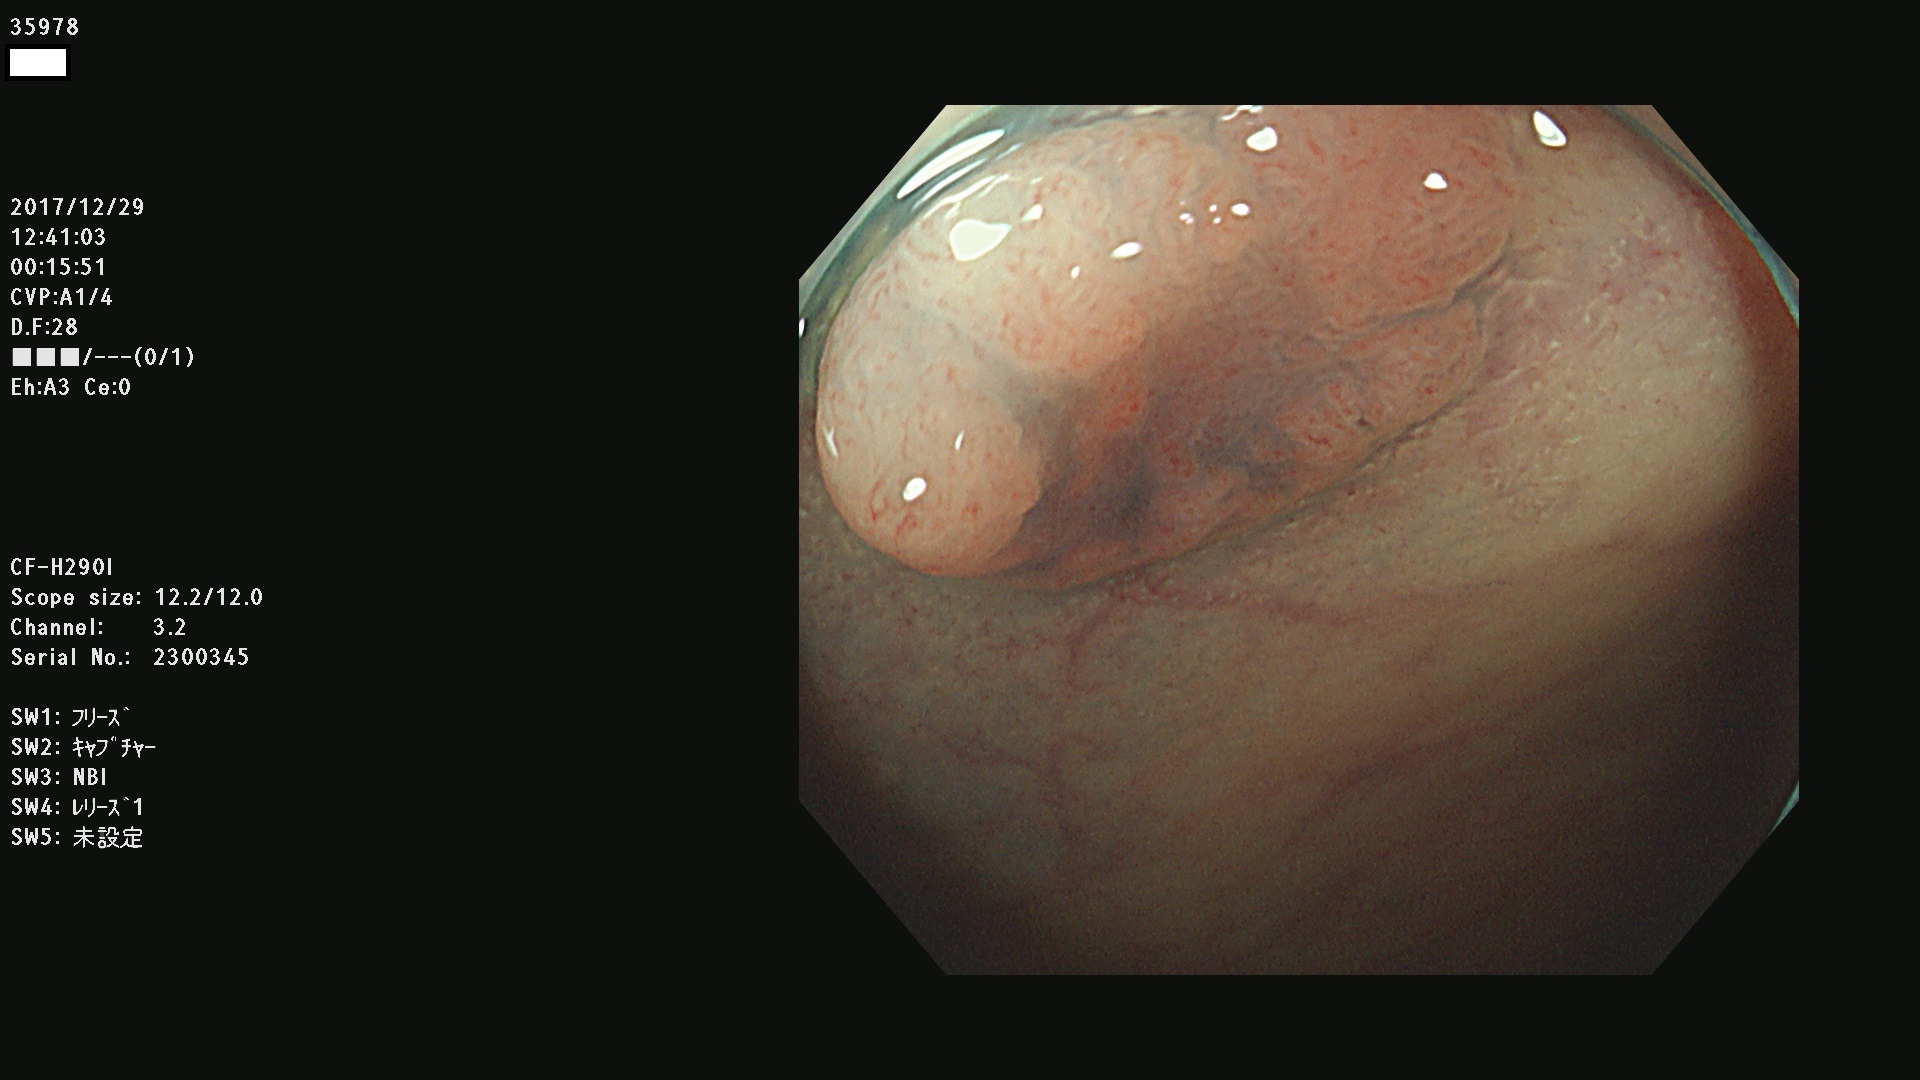

腺腫発見率43 % (カルテ番号 35900〜35999の100名の方の検査結果で集計)大腸癌検診最新情報

以下のカルテ番号の方に腺腫(Adenoma,Group3〜5)が見つかりました(集計法)

35900 35901 35904 35908 35912(SSA/Pのみ) 35914 35918 35922 35925 35926 35928 35931 35932 35933 35934 35937 35939 35943 35945 35947 35949 35951(SSA/Pのみ) 35952 35958 35959 35963 35964(SSA/Pのみ) 35965 35970 35972 35976(SSA/Pのみ) 35977 35978 35979(SSA/Pのみ) 35980(SSA/Pのみ) 35982 35983 35985 35991 35993 35995 35997 35999

発見困難で危険性の高い平坦型病変(上記100名より抽出) ![]()